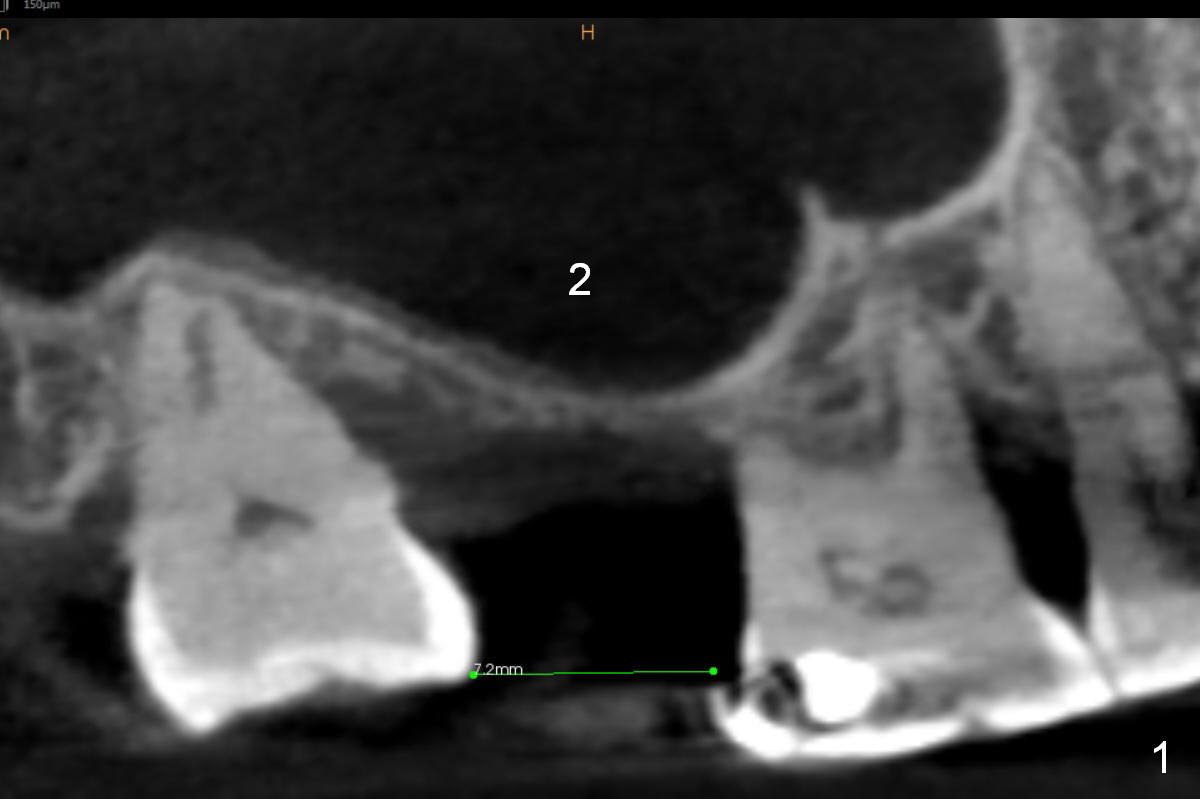

A 78-year-old man needs implant restoration at #2 in spite of limited bone height, because of severe ridge atrophy at #18 and 19. Sagittal (Fig.1-3) and coronal (Fig.4-6) sections show bone height less than 1 mm. If there is plenty of the keratinized tissue at #2, use a 4 mm tissue punch for access, followed by sinus lifter. Use fine and coarse allograft for sinus lift.